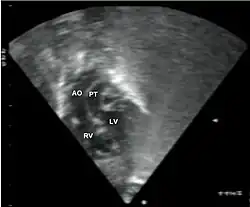

Subcostal echocardiographic view showing discordant ventriculoarterial connections together with the presence of parallel, rather than crossing, great arteries arising from the ventricles.

Transposed vessels can present with atriovenous, ventriculoarterial and/or arteriovenous discordance. The effects may range from a slight change in blood pressure to an interruption in circulation depending on the nature and degree of the misplacement, and on which specific vessels are involved.

Although "transposed" literally means "swapped", many types of TGV involve vessels that are in abnormal positions, while not actually being swapped with each other. The terms TGV and TGA are most commonly used in reference to dextro-TGA – in which the two main arteries are in swapped positions; however, both terms are also commonly used, though to a slightly lesser extent, in reference to levo-TGA – in which both the arteries and the ventricles are swapped; while other defects in this category are almost never referred to by either of these terms.